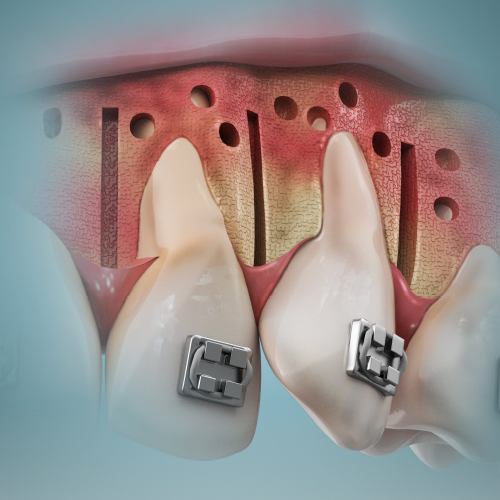

New Directions in Orthodontics

Wednesday, May 8, 2024

This Compendium eBook features a continuing education (CE) article on palatal expansion in skeletally mature adolescents and young adults who have maxillary transverse deficiencies. This eBook also includes an article on the use of clear aligner therapy in tandem with TAD–supported 3D-pri...

Orthodontic Pathways

Tuesday, November 21, 2023

This Compendium eBook features a continuing education (CE) article on guidelines for the orthodontic management of impacted maxillary central incisors. This eBook also includes a case report article on interdisciplinary team management of an esthetic-prosthetic treatment plan for a patient ...

Orthodontic Updates

Thursday, May 11, 2023

This Compendium eBook offers a continuing education (CE) article on recent minimally invasive orthognathic surgical (MIOS) procedures. The authors examine the differences between the minimally invasive and traditional orthognathic surgical techniques, and review the esthetic benefits that c...

Orthodontic Advances

Sunday, December 4, 2022

This Compendium eBook offers two continuing education (CE) articles on orthodontics. The first CE article discusses key aspects of presurgical and postsurgical orthodontics. The second CE article evaluates pre-orthodontic surgical techniques that are utilized to increase bone volume and red...

Breakthroughs In Orthodontics

Friday, December 10, 2021

This Compendium eBook offers a continuing education (CE) article on collaboration between general dentists and orthodontists. Together, through communication and partnership, orthodontists and general dentists can help ensure that the success of the orthodontic treatment lasts for the patie...

Developments in Orthodontics

Tuesday, May 18, 2021

This Compendium eBook opens with a continuing education (CE) article and in-depth case presentation of a complex iatrogenic defect. The accompanying case report explores a treatment plan developed to improve the patient’s lateral profile and lip line, obtain ideal inclination of anterior ...

Advancements in Orthodontics

Monday, November 16, 2020

This Compendium eBook offers a continuing education (CE) article that delves into all aspects of Corticotomy-accelerated orthodontics (CAO). A literature review focuses on an area of increasing concern in pediatric dentistry: early screening for sleep-disordered breathing.

Innovations in Orthodontics

Friday, May 15, 2020

This special Compendium eBook delves into factors affecting malocclusion and bone, beginning with a continuing education (CE) article on surgically facilitated orthodontic treatment (SFOT), followed by an article that features a case report in which a segmental osteotomy was performed.

Spotlight on Orthodontics

Wednesday, December 11, 2019

This special Compendium eBook provides two continuing education (CE) articles that emphasize the importance of teamwork in conjunction with orthodontics.

Advances in Orthodontics

Wednesday, November 21, 2018

Dentistry increasingly consists of many specialties that are brought together in the interest of optimal patient care. This special Compendium eBook contains two continuing education (CE) articles focusing on the role of orthodontics in cases that involve an interdisciplinary team.

Current Topics in Orthodontics

Monday, May 14, 2018

This eBook provides two continuing education articles on orthodontics. The first CE article demonstrates the use of forced eruption and a novel subperiosteal minimally invasive (a)esthetic ridge-augmentation technique, known by the acronym SMART, for the treatment of a complex iatrogenic gingival-al...

Orthodontics

Monday, April 3, 2017

This issue of Compendium's Clinical eBook Series features two continuing education articles aimed at improving orthodontics, including reducing the time needed to complete treatment as well as the use of lasers to enhance esthetic outcomes of orthodontic treatment. Download to earn 4 FREE CEU now!